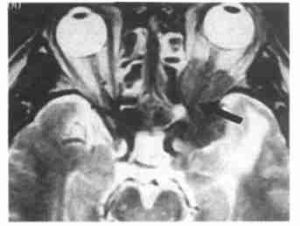

典型的臨床表現診斷並不困難。最後診斷還需要CT。水平和冠狀CT顯示眶內壁或眶底骨折,眶內軟組織或肌肉向鼻旁竇突出。